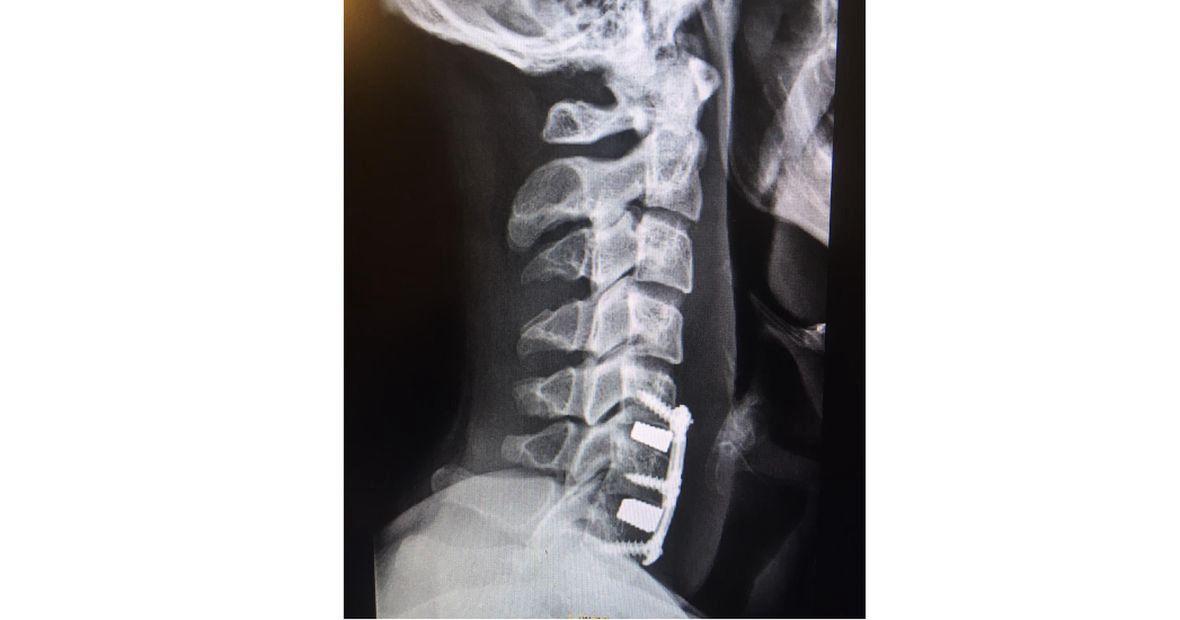

– Lekarz wyjaśnił mi, że zainstalują mi w szyi płytki, które zostaną tam już na całe życie. Przyznał, że operacja może się skończyć paraliżem rąk i nóg, wytrzeszczem oczu, albo nawet śmiercią. Najtrudniejsze w tym momencie było to, że nie mogłem zobaczyć się z najbliższymi. A przecież nie wiedziałem, czy jeszcze kiedyś ich zobaczę – mówi Mateusz.

Pierwsze, co zrobił po operacji, to sprawdził, czy wszystko działa: - Lewa ręka się rusza. Prawa też. Mogę przełknąć ślinę. Mam głos. Ulga.